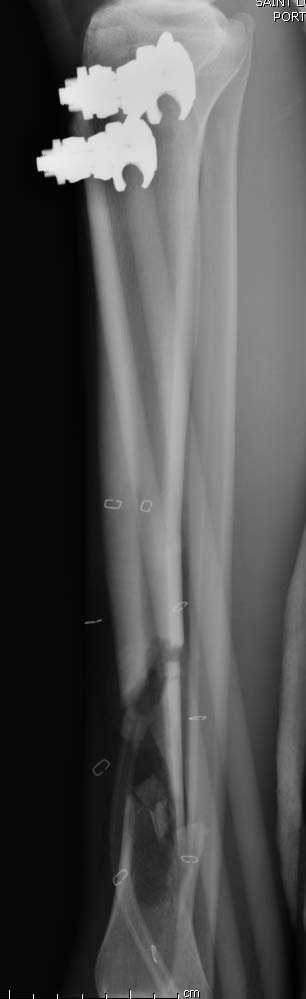

Данный случай не огнестрельная рана, а результат мотоциклетной аварии.

Независимо от повреждения при таких обширных дефектах мягких и костной

тканей применяется схожая тактика. Как видно, после нескольких I&D для

создания “pseudo membrane” применили цилиндрический блок из цемента.

Дефект мягких тканей закрыли свободным Anterior Thigh Graft. Из малого

доступа цилиндр удален небольшими кусочками, а пространство заполнили

бусами для освобождения пространства. По мере приближения регенерата

освободили пространство удалением бус через небольшой разрез. Этап

созревание регенерата можно было ускорить усилением интрамедуллярным

гвоздем, но решили закончить методом Илизарова.